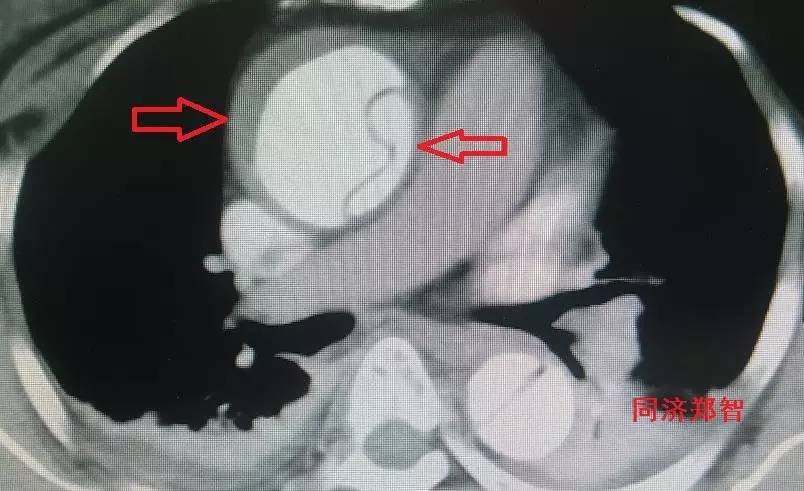

② Stanford A型 主动脉壁间血肿的CTA重建(图2),提示升主动脉和胸降主动脉的主动脉壁均有病变(红箭头所示)。

图2